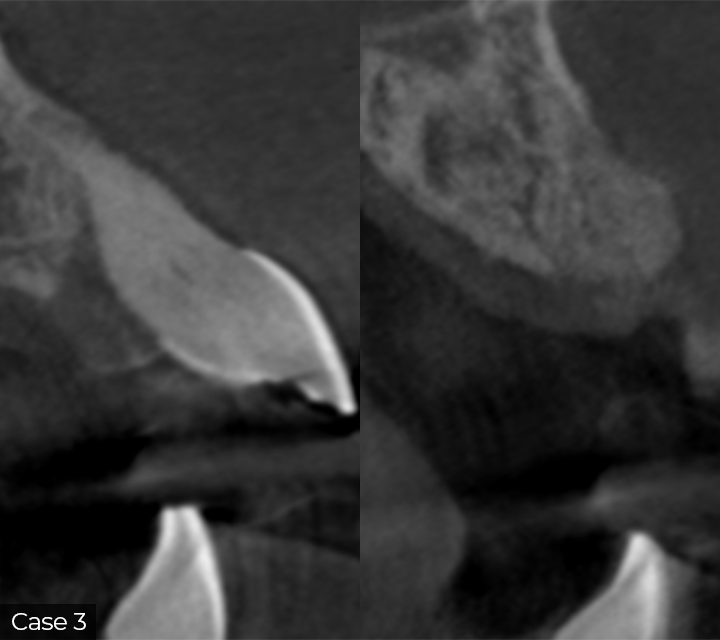

This course offers a focused overview of key surgical techniques in implant and periodontal treatment. Topics include guided bone regeneration principles, biomaterial selection, autogenous bone harvesting, and management of compromised sockets. Emphasis will be placed on soft tissue handling, including flap advancement, the LASSO suturing technique, and free gingival grafts. Participants will also learn how to manage complications effectively.

Director’s Clinical Cases

This course offers a focused overview of key surgical techniques in implant and periodontal treatment. Topics include guided bone regeneration principles, biomaterial selection, autogenous bone harvesting, and management of compromised sockets. Emphasis will be placed on soft tissue handling, including flap advancement, the LASSO suturing technique, and free gingival grafts. Participants will also learn how to manage complications effectively.

Director’s Clinical Cases